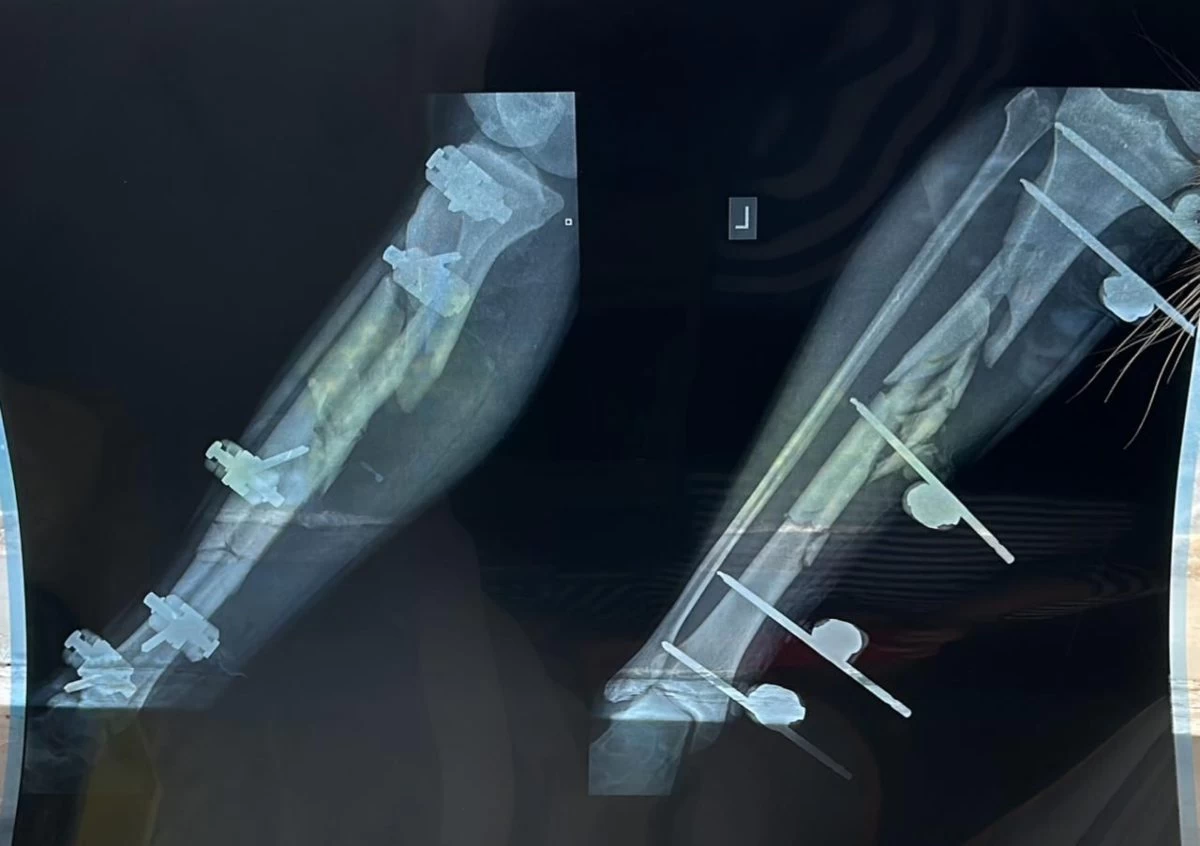

Александрдың жараланған аяғы. Оның аяққа тұрып кетуі үшін әлі біраз уақыт қажет

«Бауырымды ауруханаға әкелгенде дәрігерлер енді бір-екі сағат болғанда, құтқарып қалу мүмкін болмайтын еді деп айтты. Көп қан жоғалтқан. Осы уақытқа дейін ол өздігінен тыныстай алмағандықтан, ИВЛ аппаратына қосулы болды. Александрдың өмірі үшін қатты алаңдадық. Оның аяққа тұрып кетуі үшін әлі біраз уақыт қажет. Алда бірнеше жылдарға созылатын оңалту шаралары тағы бар. Інім спортқа жақын болатын. ҚАЖД қызметкерлері арасында ұйымдастырылатын жарыстарға үнемі қатысып, жүлделі орындардан көрінетін. Бүгіндері оның мына жағдайына қарап, адамдардың соншалықты айуандыққа баратындығына сене алар емеспіз», — дейді Александардың ашынған ағасы.